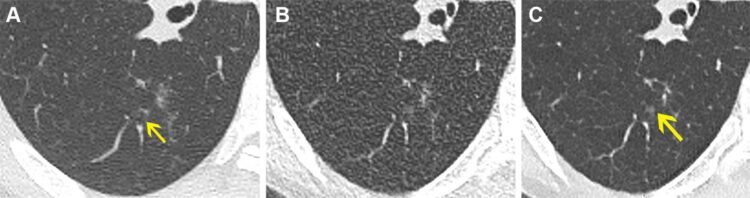

초저선량 CT는 환자의 방사선 노출량을 줄일 수 있지만 이미지를 거칠게 만드는 노이즈가 있어 정확한 판독이 쉽지 않은 단점이 있다.

연구팀은 딥러닝 알고리즘을 적용해 초저선량 스캔에서 노이즈를 모두 제거했다. 그 결과 초저선량 CT의 이미지 품질과 선명도가 크게 개선돼 진단 정확도가 높아졌고 결절도 쉽게 식별됐다.

한 남성 환자의 경우 정상 선량 CT에선 폐가 정상이었다. 초저선량 CT의 경우 두 판독자 모두 노이즈로 인해 양성 바이러스 감염이라고 봤다. AI로 노이즈를 제거하자 정상으로 다시 판독됐다.